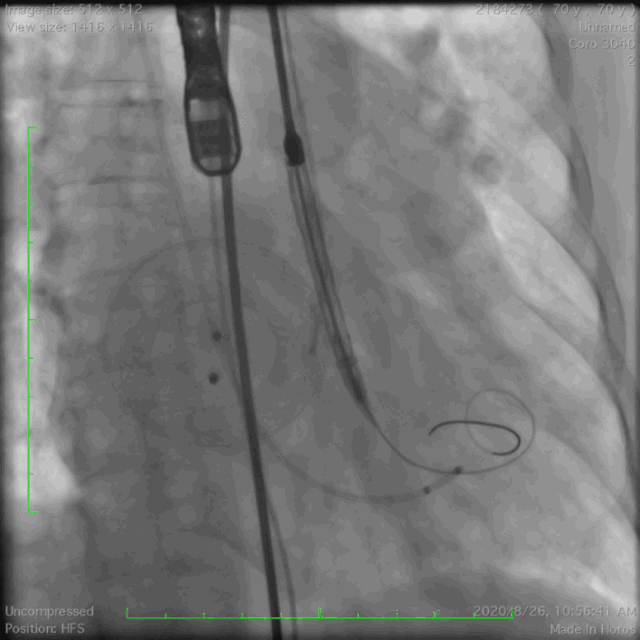

● 手术过程

瓣膜定位